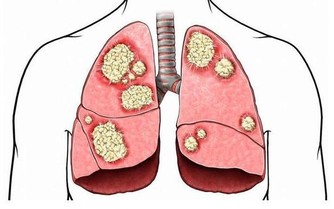

曾在門診見一久咳不癒的年輕姑娘,臉色萎黃,身材瘦弱。依照我的經驗,她肯定是當代社會“ 時髦瘦身理論 ”的受害者。詢問之下,果然如此,平時這姑娘幾乎不吃主食。

最後,她的檢查結果出來了,是肺結核。拿著報告單,可憐的姑娘欲哭無淚,一個靠打工賺取微薄收入的小女子,拿什麼來承擔後面昂貴的醫藥費?

主食不足,很可能是肺結核的重要原因之一。

有一個朋友的母親,每當有人去她家時,都會大講她的不凡經歷。年輕的時候,她得了肺結核,住在專治肺結核的醫院裡。沒幾天,就有不幸死亡的病人被抬出去,她看著心中特別害怕。

那時,她也不想吃飯,但她更渴望活下去,所以,每餐吃飯時,她總是非常努力,想方設法地把醫院配給她的兩個大饅頭嚥下去。雖然經常嚥下去就吐,但她仍然堅持著,就這樣吃了吐,吐了吃。在同樣的治療條件下,最後她的病慢慢開始好轉。

從這個例子看,主食的作用豈可小覷?